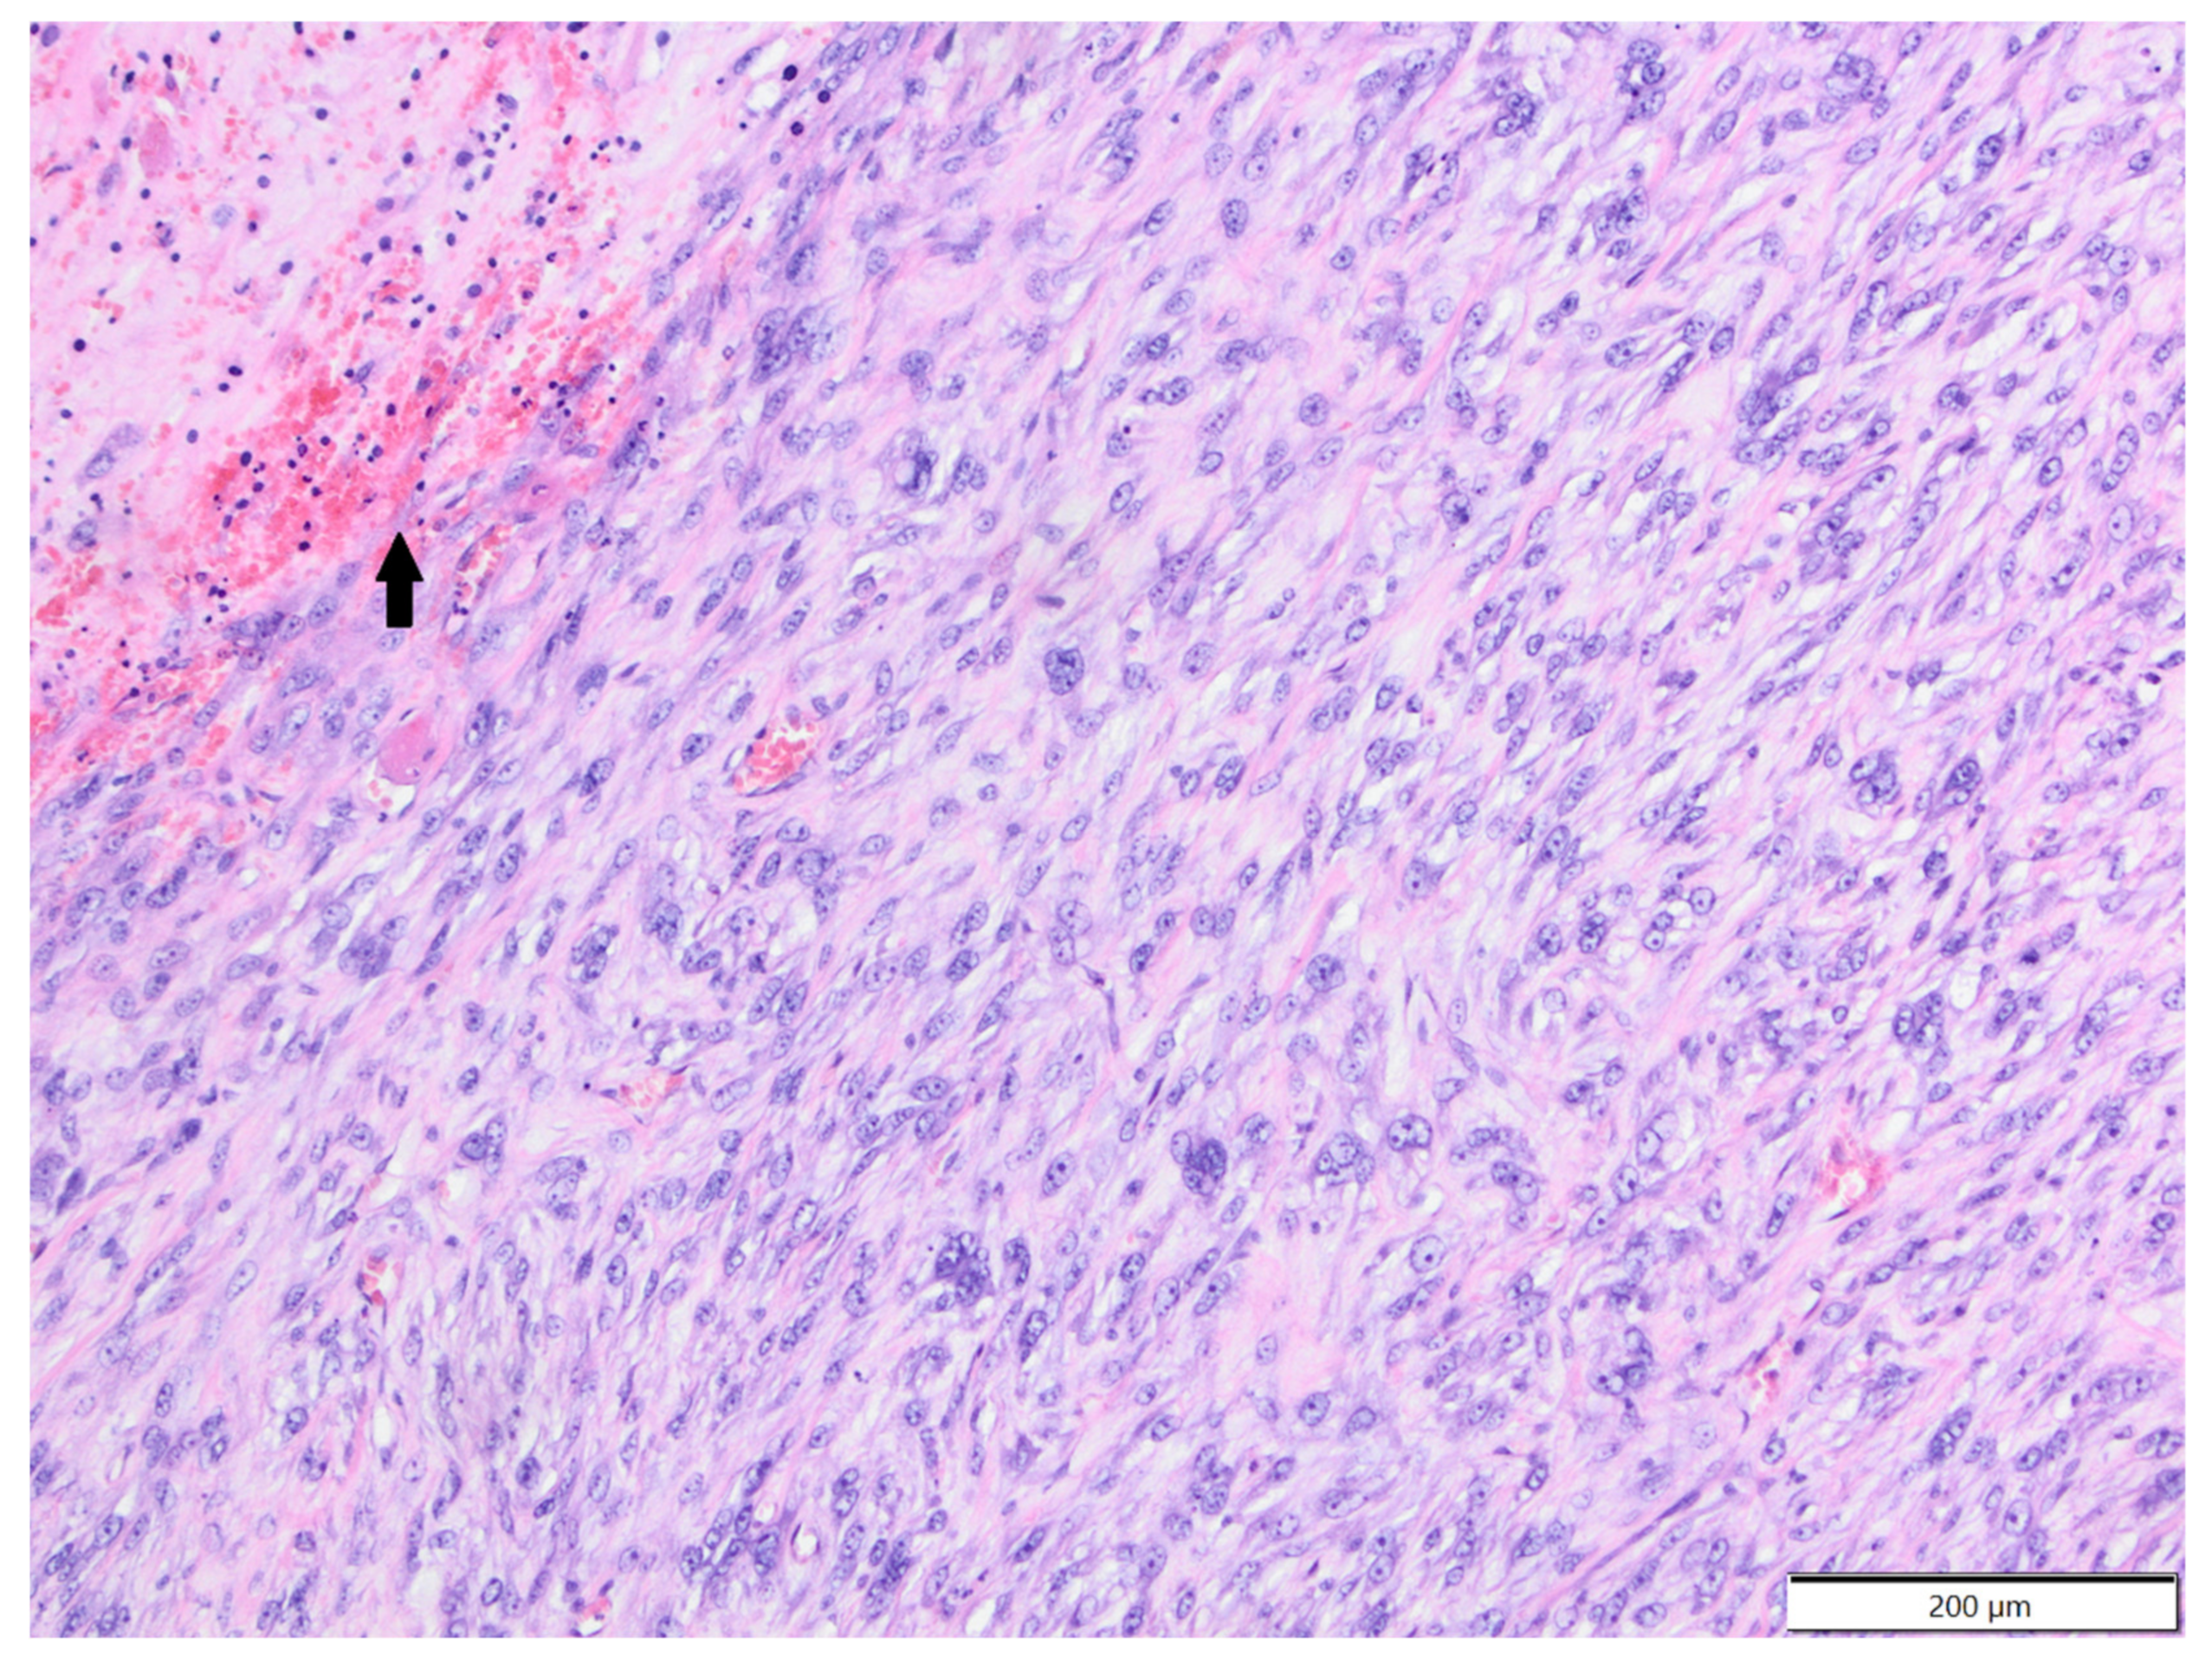

Figure 7.

Fibrosarcoma, area unspecified, chinchilla. There are bundles of spindle to oval tumour cells and moderate amount of collagen fibres between them. Tumour cells undergo focal necrosis (arrow). HE.